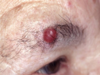

BCC clinical presentation

- Slow growing lump which may go on to form a non-healing ulcer (centrally – rodent ulcer).

- Pearly/translucent edge with visible dilated blood vessels.

- painless and often ignored

*

BCC describe central ulceration